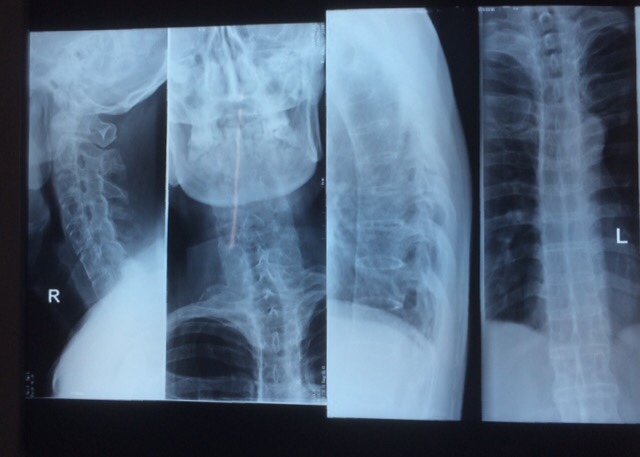

辅助检查:颈、胸段脊柱向右侧倾斜,腰段脊在向左倒倾斜,生理弯曲度变直、颈、胸、腰椎各椎体呈竹节样改变,骨质呈疏松征象,颈、胸、腰椎各椎间隙及椎小关节 关节不同程度变窄、消失。骶髂关节模糊,双髋关节关节周围诸骨不同程度骨质增生改变,骶髂及双髋关节间隙变窄、消失。